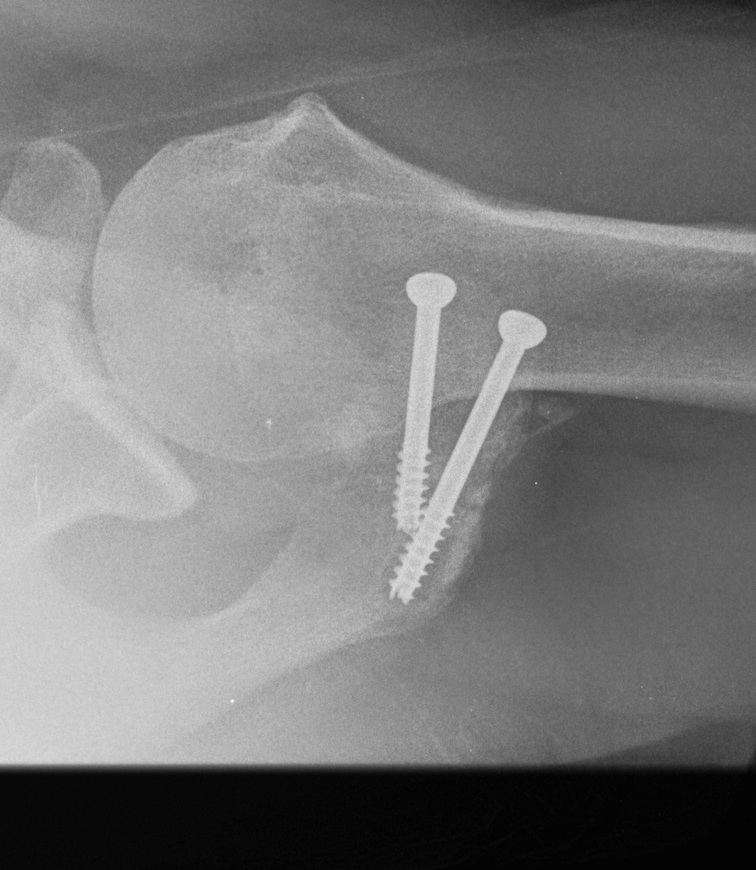

2. ORIF

Indications

Large fragment / mesoacromion

- take down non union

- bone graft / 2 x AP 3.5 mm screws / TBW

- especial care with deltoid reattachment

Outcomes

Atinga et al J Should Elbow 2018

- 32 cases treated with screw fixation and bone graft

- 100% union at 3 months

- 1 infection, 1 seroma, 4 removal of metal work

Risks

Nonunion

- remove screws

- arthroscopic resection

Non union with evidence of lysis around screws